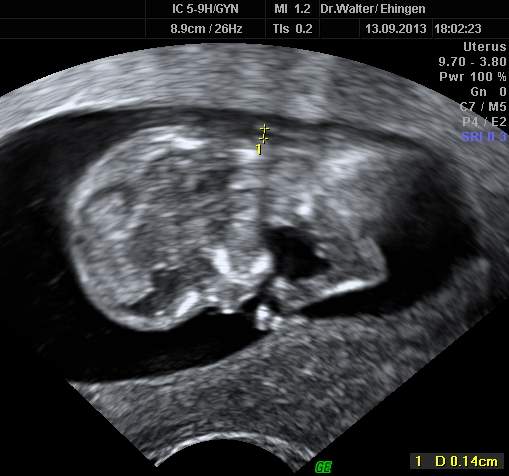

Am Ende des ersten Schwangerschaftsdrittels findet man häufig eine Wasseransammlung (Nackentransparenz) unter der Haut des kindlichen Nackens. Ist diese Schicht größer als normal, kann dies auf chromosomale Anomalien oder andere Erkrankungen des Kindes hinweisen (z. B. Herzfehler).

Durch die Messung der kindlichen Nackentransparenz (NT-Messung) kann von der 12. bis 14. Schwangerschaftswoche durch zertifizierte Ärzte eine individuelle Risikoberechnung in Bezug auf die Trisomie 21 durchgeführt werden.

Die Messung erfolgt durch eine vaginale oder abdominale Ultraschall-Untersuchung.

| unauffällige Nackentransparenz | exakte Darstellung im hochauflösenden Ultraschall | auffällige NT, weitere Diagnostik erforderlich! |

Diese Untersuchungen bieten keine Diagnose, sondern eine individuelle Risikoabschätzung. Ein auffälliges Testergebnis bedeutet nicht, dass das Kind eine Chromosomenanomalie oder einen Herzfehler hat, sondern es zeigt an, ob ein höheres Risiko besteht. Dann sollte ggfs. eine weiterführende Diagnostik erfolgen. Umgekehrt kann das Risiko bei entsprechender NT-Messung sich auch vermindern. Ein sicherer Ausschluss von Chromosomenstörungen ist letztlich nur durch eine Fruchtwasserpunktion oder Chorionzottenbiopsie möglich.